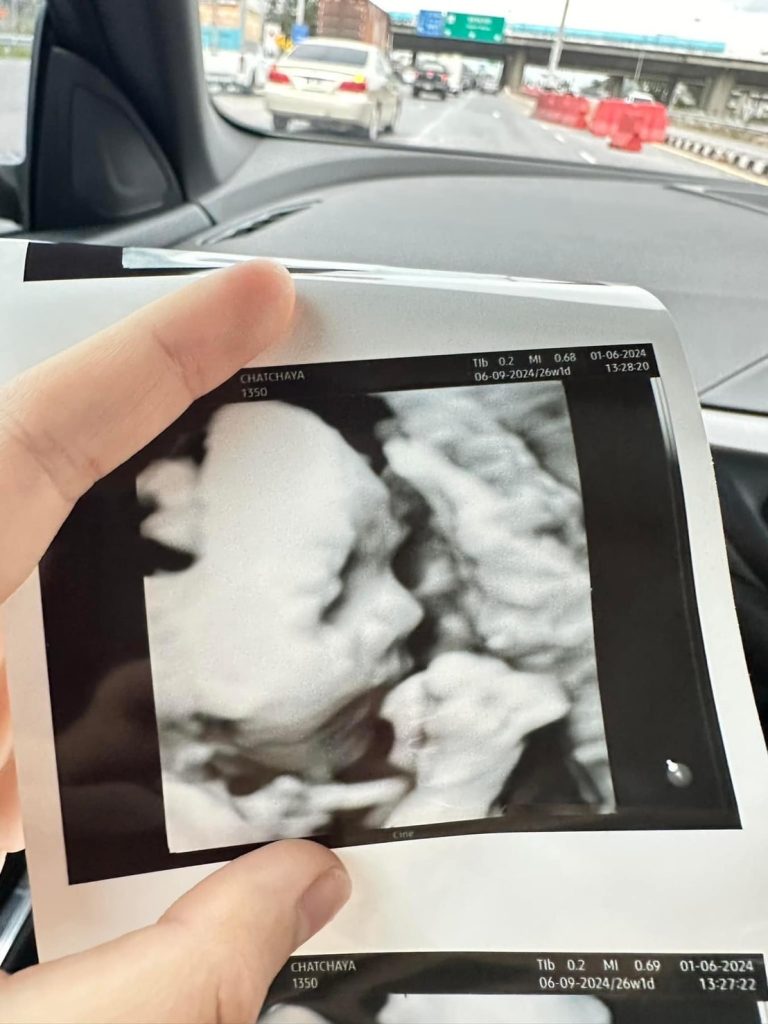

ทำเอาคุณแม่มือใหม่อย่าง ธัญญ่าอาร์สยาม ใจฟู ได้เห็นวิวัฒนาการของลูกใน 27 สัปดาห์

บอกเลยอะค่ะเตรียมตัวรับมือการเป็นคุณแม่ป้ายแดงที่จะได้เจอหน้าลูกในเร็ววันนี้ด้านธัญญ่าตื่นเต้นเตรียมของต้อนรับสมาชิกใหม่ไวให้ลูกเต็มบ้าน และ คอยอัพเดทผ่านโซเชียลให้กับบรรดาเอฟซีแฟนคลับได้ลุ้นรอเชียร์กันไปตามตามกันแล้วค่ะ